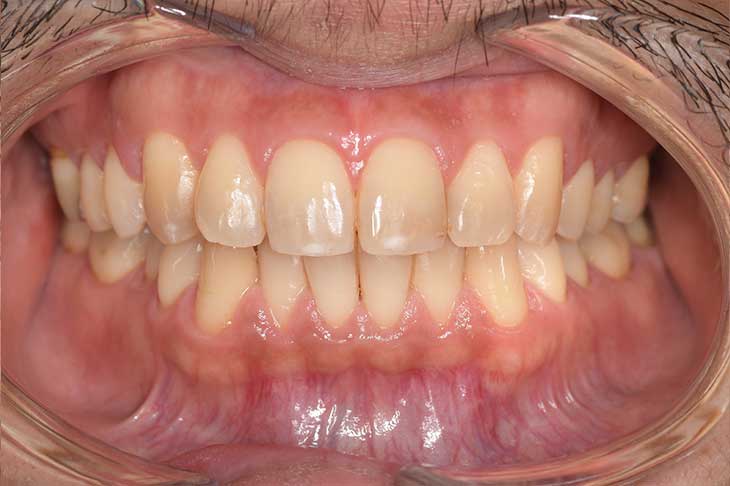

CASE 2

Before

After

基本情報

| 年齢・性別 | 30代・男性 |

| 主訴 | 歯石を取りたい |

| 治療内容 | 超音波スケーラーでの歯石除去 |

| 治療期間 | 60分 |

| 治療費 | 初診料を含め約4,500円 |

| リスク・副作用 | 歯ぐきに違和感や痛みを覚える場合がある。 1週間程度、歯を磨くといつもより出血することがある。 腫れていた歯ぐきが引き締まることで歯ぐきが下がった様に見える。 歯ぐきが下がることで歯がみしやすくなることがある。 一時的に歯の動揺(ゆれ)が増す場合がある。 |